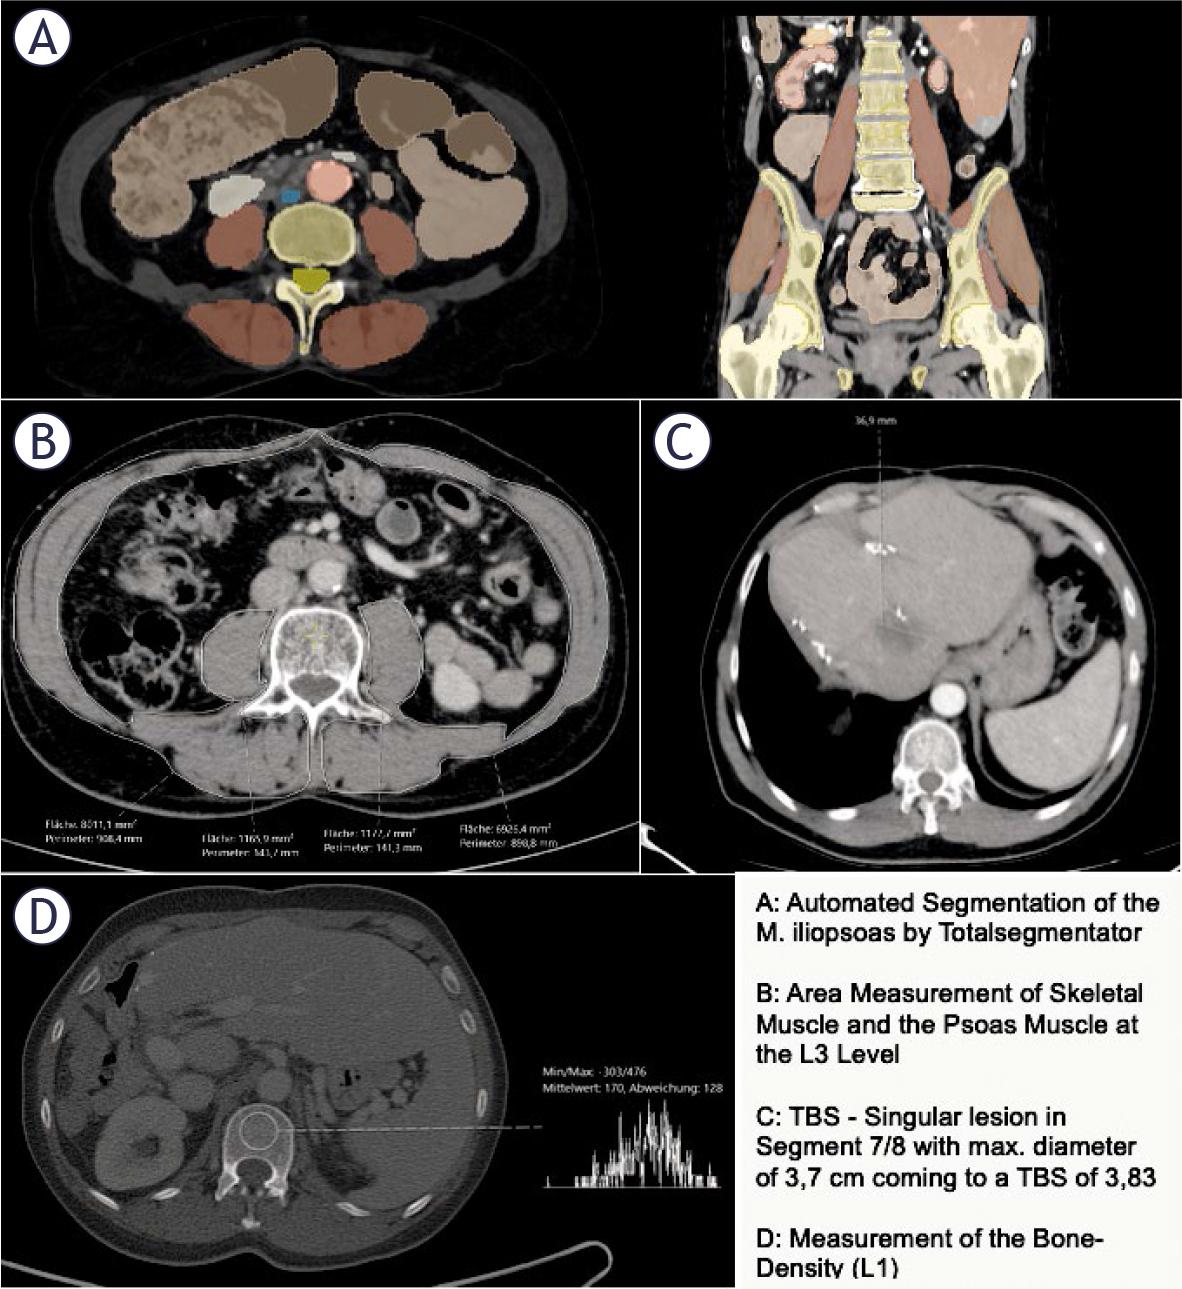

To determine the PMI, we used the same pre-interventional images as for the PMVI. Area of the psoas muscle was measured at the level of the third lumbar vertebra using the measurement function of our image archiving system, Sectra, in cm2 (Figure 1B). The PMI was then calculated by determining the combined area of the bilateral psoas muscle, divided by the height squared (cm2/m2). The SMI was measured at the level of L3 corresponding to the PMI (Figure 1B). The SMI was calculated by determining the area of skeletal muscle divided by height squared (cm2/m2).

Example of imaging data acquisition of psoas muscle volume index (PMVI), psoas muscle index (PMI), skeletal muscle index (SMI), tumor burden score (TBS) and bone density

To determine the bone density, a circular region of interest (ROI) was placed in the trabecular bone of the vertebral body of the first lumbar vertebra (L1) (Figure 1, D). The mean CT density (HU) was measured by placing a ROI in the axial slice. During the placement of the ROI, areas that could distort the CT density measurement (such as focal lesions, the internal posterior venous plexus, or imaging-related artifacts) were avoided. The same venous images as those used for the PMVI and PMI determination with a slice thickness of 3.0 mm were used for the analysis. This measurement is often used as an indirect marker of bone quality and can be correlated with overall muscle mass and body composition.22,23.

To determine the TBS, the number of metastases and the extent of the largest lesion were recorded from the pre-interventional CT (the same as for PMVI, PMI, and L1). TBS was defined using a Cartesian coordinate system, where the maximum tumor diameter (on the x-axis, in cm) and the number of lesions (on the y-axis) were considered. TBS was designed to assess the extent of the liver metastases and their potential impact on patient prognosis. The number of lesions and the maximum diameter of the largest lesion were extracted from the written report of the pre-interventional CT scan and independently verified by a secondyear radiology resident.